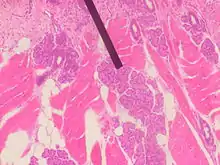

A glândula de von Ebner no corpo humano.

As glândulas serosas de von Ebner, também conhecidas por glândulas gustativas ou apenas glândulas de von Ebner são glândulas exócrinas encontradas na boca.[1] Estão presentes nas papilas foliadas e circunvaladas da língua. São glândulas exócrinas serosas, que sintetizam e secretam uma secreção serosa rica em água, eletrólitos e lipase lingual, a fim de promover uma limpeza dos sulcos e da mucosa da cavidade oral. Seus ductos desembocam nos sulcos entre as papilas.[carece de fontes]